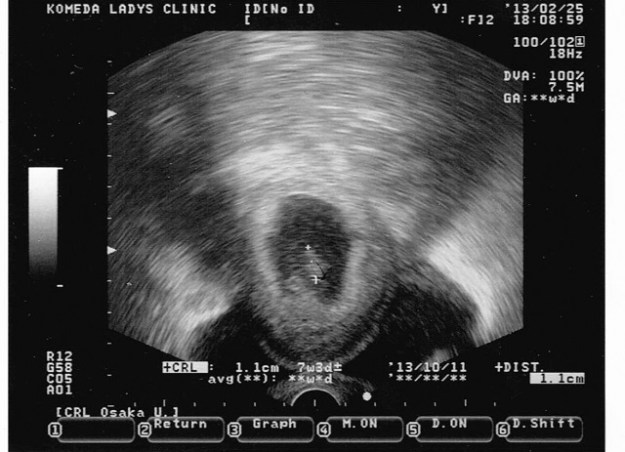

03 - 7SA

7SA

A contrario, grosse note positive, car lors de ce rendez vous, une 3ème écho à été réalisée, et nous avons vu un petit haricot de 1cm. C’est idiot mais ça permet de vraiment réaliser qu’il y a quelque chose qui grossit dans le ventre de ma femme. (Quand je dis « nous avons vu », en fait ma femme à vu quelque chose en direct à l’écho et moi je me suis contenté de la photo de l’écho -_-‘ ).